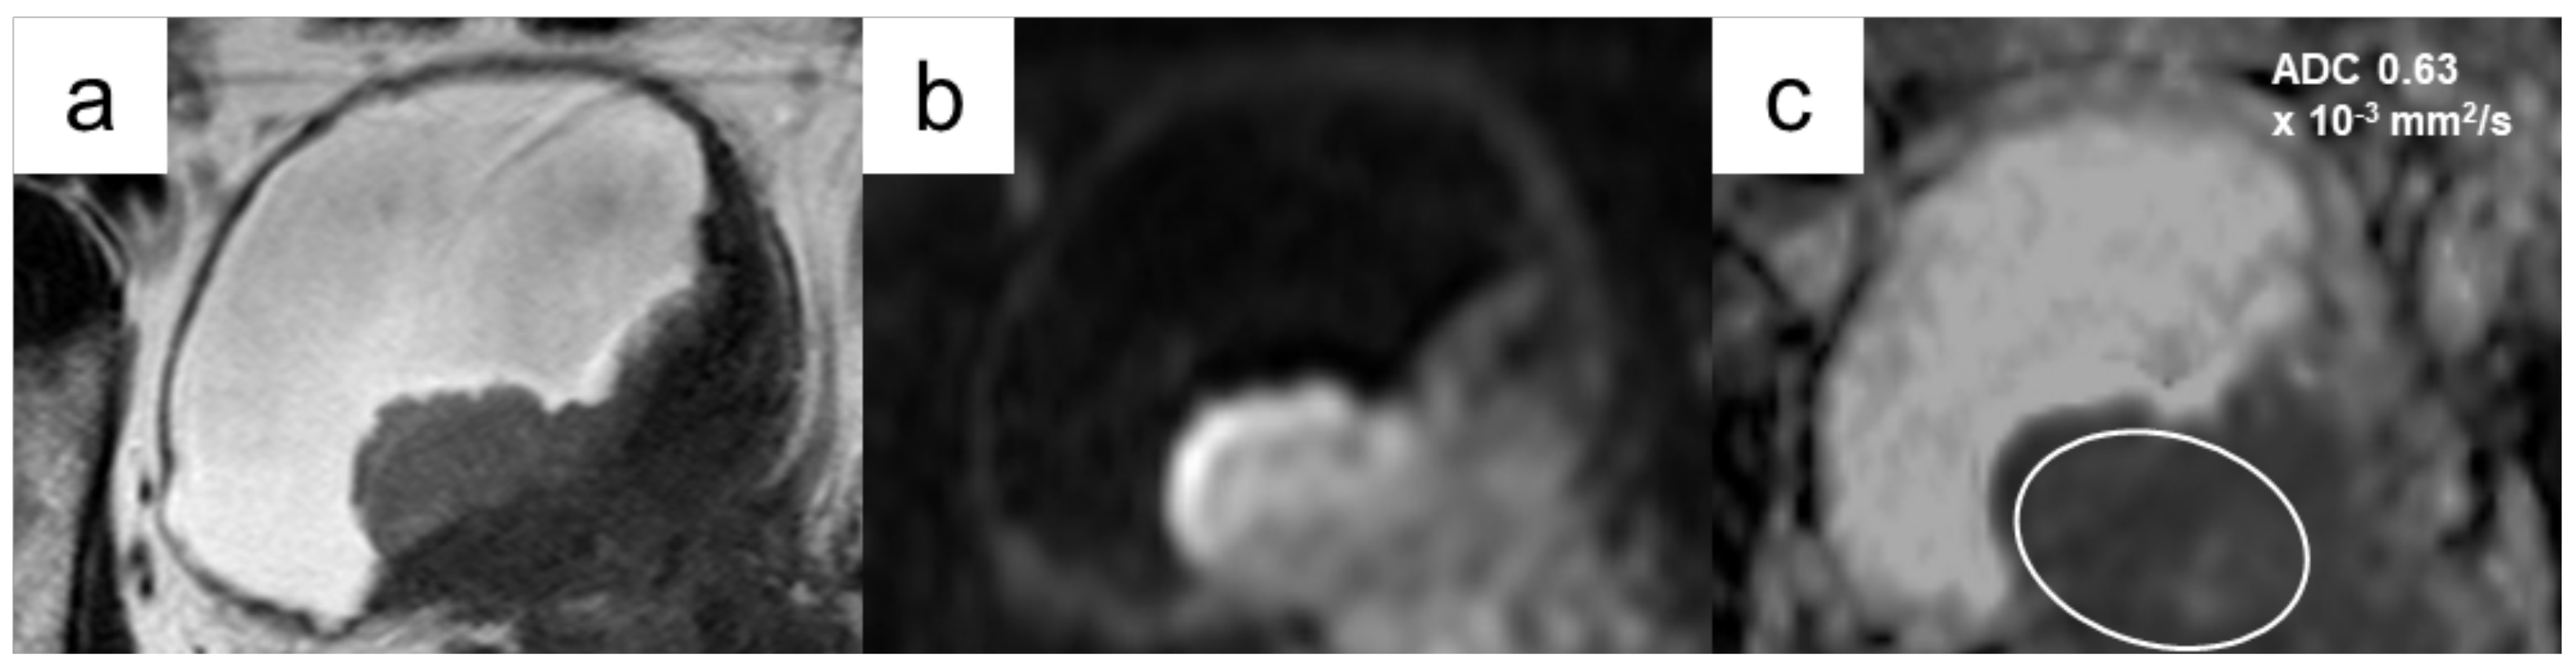

3.4.2. Diagnostic Performance of ADC Values to Differentiate High-Grade Disease from Low-Grade Disease